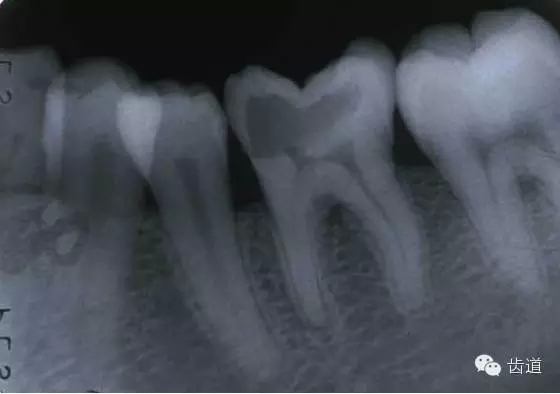

左下6底穿

左上6底穿